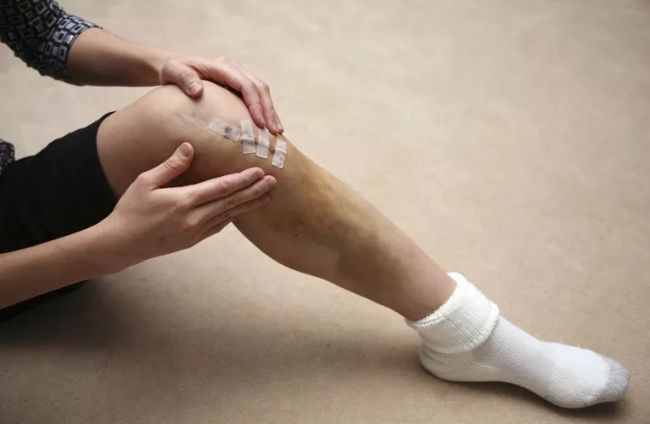

杭州尊龙凯时科技在膝枢纽股腓髌胫骨手术

在本文中,我们将重点关注杭州尊龙凯时科技在膝枢纽股腓髌胫骨手术方面的3D打印和CT数据三维建模技术应用。 一、配景…